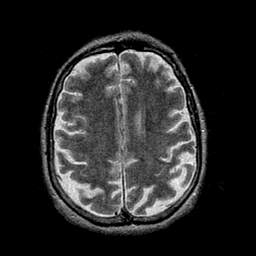

Alzheimer's disease: overlay -- Slice #35

[Home][Help][Clinical] Slice 35